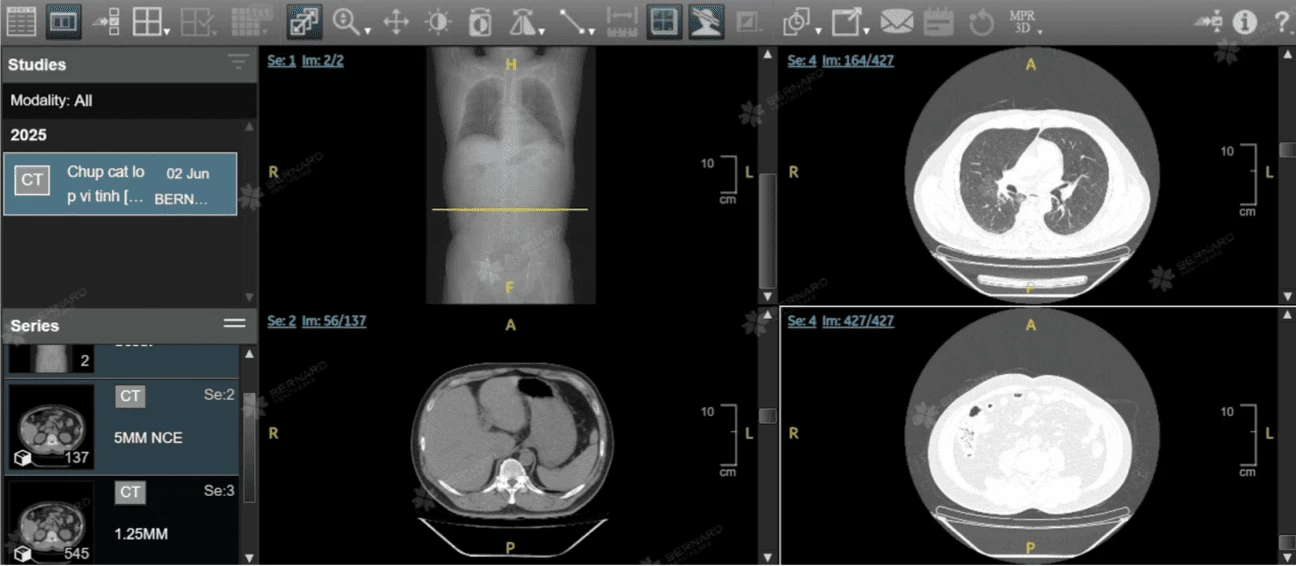

Hình ảnh CT Scan trên hệ thống AI PACS tại Bernard

CT scan với khả năng tái tạo bộ phận, mô, xương trong cơ thể thông qua hình ảnh các lát cắt hoặc mặt cắt ngang của cơ thể cơ thể người chi tiết và chính xác, hỗ trợ bác sĩ phát hiện sớm các tổn thương dù rất nhỏ trong phổi mà các phương pháp như chụp X-quang không thể nhìn thấy

Hình ảnh học từ CT toàn thân giúp bác sĩ quan sát rõ tổn thương bên trong cơ thể mà mắt thường hay khám lâm sàng không thể thấy được

Hệ thống CT Scan được Bernard tận dụng triệt để trong tầm soát và phát hiện sớm các tổn thương lành tính; Tổn thương tiền ung thư (phổi, gan, vú, giáp, cổ tử cung, dạ dày, đại trực tràng,...); Ung thư giai đoạn sớm và ung thư (trích xuất từ hệ thống PACS tại Bernard)

Ngoài khả năng phát hiện ung thư phổi, CT Scan còn giúp phát hiện các bất thường trong ổ bụng với độ chính xác 95%. Các bác sĩ sử dụng CT để phân tích gan hoặc tuyến tụy, túi mật, bàng quang, khối u thận - Viêm đại tràng, viêm ruột, viêm ruột thừa - Sỏi thận, sỏi bàng quang, các tổn thương nội tạng (trích xuất từ hệ thống PACS tại Bernard)